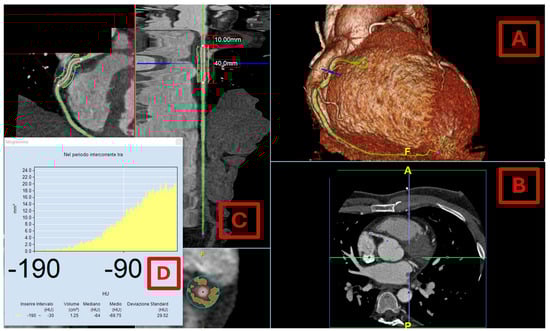

5.3. CCT Evaluation of EAT

5.4. PCAT Assessment Through CT

- Nogajski, Ł.; Mazuruk, M.; Kacperska, M.; Kurpias, M.; Mączewski, M.; Nowakowski, M.; Mączewski, M.; Michałowska, I.; Leszek, P.; Paterek, A. Epicardial Fat Density Obtained with Computed Tomography Imaging—More Important than Volume? Cardiovasc. Diabetol. 2024, 23, 389. [Google Scholar] [CrossRef]

- Marwan, M.; Koenig, S.; Schreiber, K.; Ammon, F.; Goeller, M.; Bittner, D.; Achenbach, S.; Hell, M.M. Quantification of Epicardial Adipose Tissue by Cardiac CT: Influence of Acquisition Parameters and Contrast Enhancement. Eur. J. Radiol. 2019, 121, 108732. [Google Scholar] [CrossRef] [PubMed]

- Hell, M.M.; Achenbach, S.; Schuhbaeck, A.; Klinghammer, L.; May, M.S.; Marwan, M. CT-Based Analysis of Pericoronary Adipose Tissue Density: Relation to Cardiovascular Risk Factors and Epicardial Adipose Tissue Volume. J. Cardiovasc. Comput. Tomogr. 2016, 10, 52–60. [Google Scholar] [CrossRef]

- Eisenberg, E.; McElhinney, P.A.; Commandeur, F.; Chen, X.; Cadet, S.; Goeller, M.; Razipour, A.; Gransar, H.; Cantu, S.; Miller, R.J.H.; et al. Deep Learning-Based Quantification of Epicardial Adipose Tissue Volume and Attenuation Predicts Major Adverse Cardiovascular Events in Asymptomatic Subjects. Circ. Cardiovasc. Imaging 2020, 13, e009829. [Google Scholar] [CrossRef] [PubMed]

- Ding, X.; Terzopoulos, D.; Diaz-Zamudio, M.; Berman, D.S.; Slomka, P.J.; Dey, D. Automated Pericardium Delineation and Epicardial Fat Volume Quantification from Noncontrast CT. Med. Phys. 2015, 42, 5015–5026. [Google Scholar] [CrossRef]

- Commandeur, F.; Goeller, M.; Razipour, A.; Cadet, S.; Hell, M.M.; Kwiecinski, J.; Chen, X.; Chang, H.-J.; Marwan, M.; Achenbach, S.; et al. Fully Automated CT Quantification of Epicardial Adipose Tissue by Deep Learning: A Multicenter Study. Radiol. Artif. Intell. 2019, 1, e190045. [Google Scholar] [CrossRef]